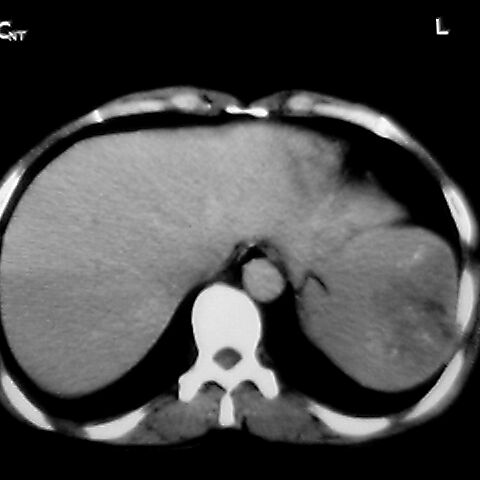

女 48岁 食道癌术前体检发现脾占位。

脾胀内部巨大低密度肿块,边界清或不清,中心坏死,轻度增强,内见散在钙化,结合食道癌病史多考虑:转移癌.

1肝右下叶小囊肿2右肾上极囊肿或错构瘤3脾脏不典型血管瘤可能性大.

脾脏低密度灶伴钙化,增强化明显,中心见液化坏死灶,强化延时明显。考虑血管瘤。转移瘤待排。